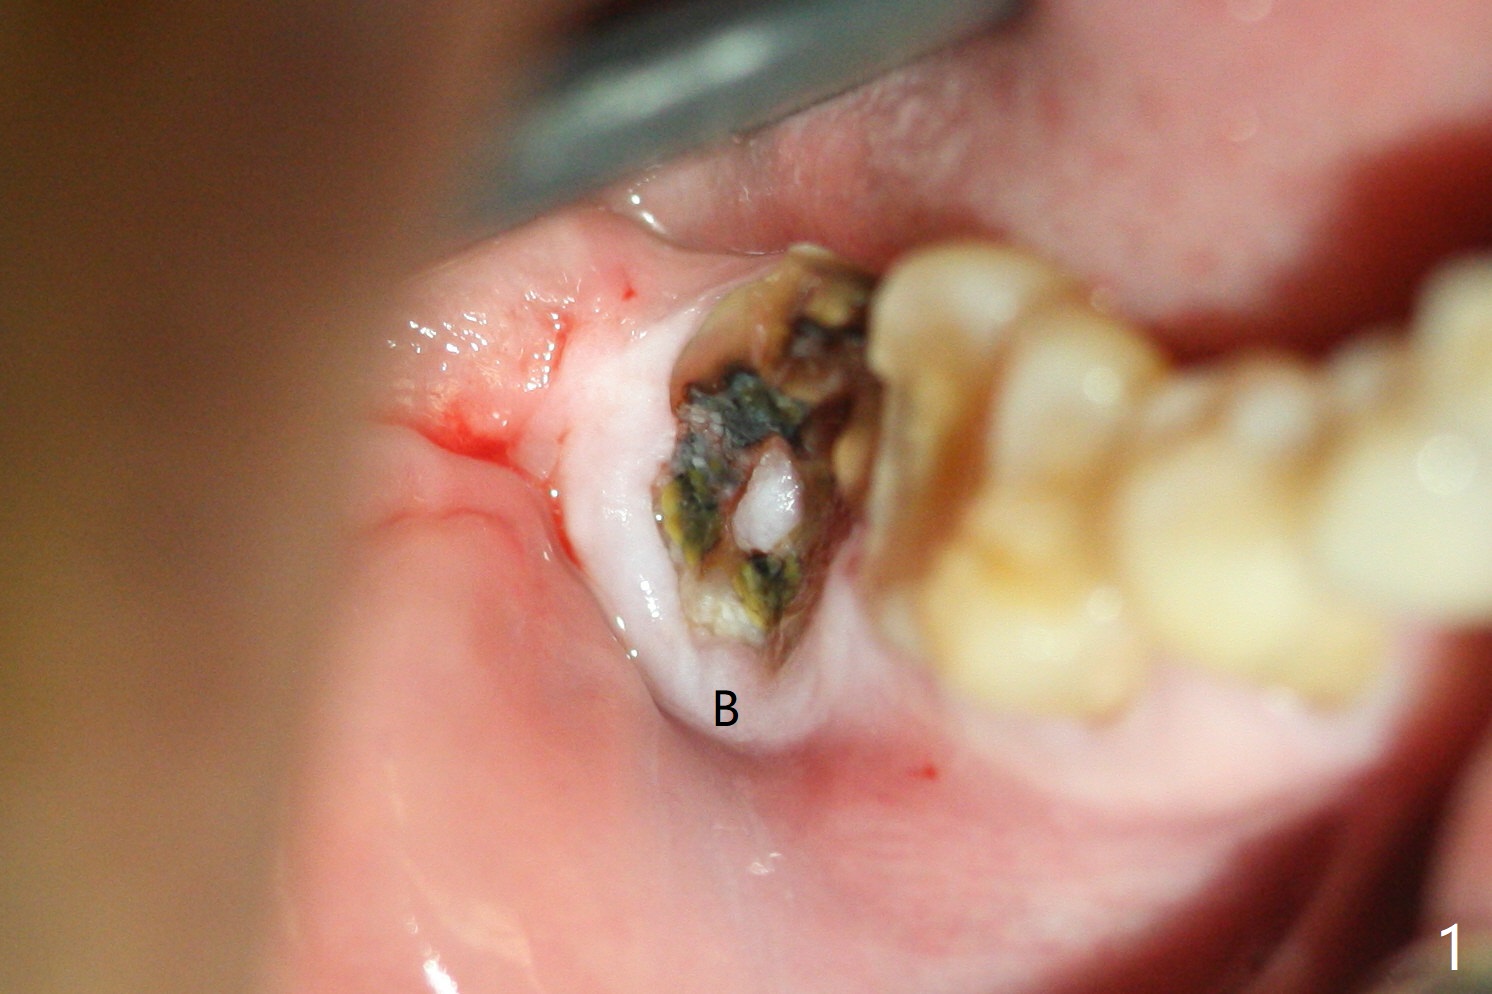

The residual roots of the tooth #31 are lower buccal (Fig.1 B), which in fact is molded and worn by the supraerupted tooth #2. When the tooth is extracted (Fig.2) and an implant, abutment (Fig.3 gold colored) and allograft (*) are placed, the abutment has to be trimmed. An atypical immediate provisional is fabricated by spreading setting acrylic over the abutment and bone graft (Fig.4 P) with occlusal equilibrium. Advantages of the guided surgery are good position (Fig.3 buccolingual), trajectory and depth (Fig.5,6) of the implant. The buccodistally exposed implant threads are packed with allograft in sufficient amount (Fig.3,5,6 *). The atypical immediate provisional breaks down and dislodges 3 weeks postop (Fig.7). In fact the implant plateau is exposed buccally. A monojet is given to the patient for self cleansing. He is instructed to return in 3 weeks. The exposed implant threads are covered 1.5 months postop (Fig.8). Incomplete abutment seating (Fig.9 <) was not noted until 1 year 3 month post cementation when the crown was mobile (Fig.10). A 6x3 mm healing abutment is placed. Three days later, the crown is sectioned and separated from the abutment. The latter returns to place; due to angulation associated with PA, the gap between the implant and abutment is indistinct (Fig.11). Bitewing is taken; the gap exists (Fig.12 <). The abutment seems to be seated deep; there is apparently soft tissue interference. A 5.2x4(2) mm abutment remains incompletely seated (Fig.13 >). A 5.2x4(3) mm one is completely seated (Fig.14 <). Zirconium crown with an access hole is cemented in the mouth. The crown and abutment is then removed for residual cement removal and reseated and torqued (Fig.15). Four months later, the Zirconium crown is fractured (Fig.16). Impression is retaken for high noble metal crown without access hole for strength (Fig.17).